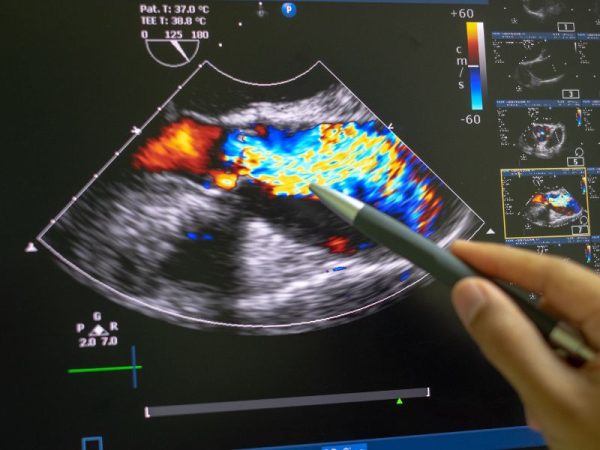

Exames de imagem produzem fotos do seu corpo. Exemplos comuns são raio‑X, ultrassom, mamografia e tomografia. Eles identificam tumores, fraturas, cálculos e alterações anatômicas que o laboratório não vê.

- Ecocardiograma: quando há sopro novo, palpitações ou antecedentes familiares de cardiomiopatia.

- Ecocardiograma e ecografia vascular (carótidas/AAA): avaliam função cardíaca e risco de aneurisma ou estreitamento das artérias.